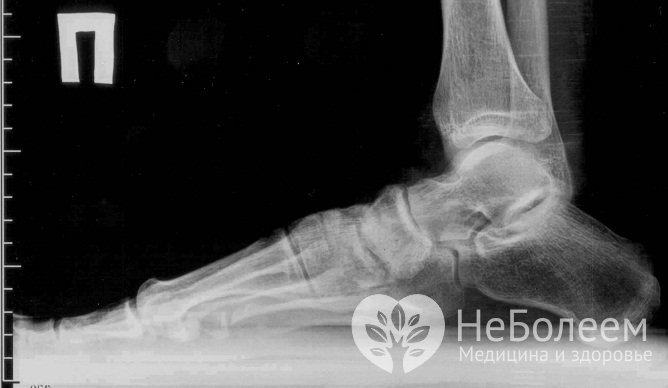

С целью подтверждения диагноза, а также для определения стадии заболевания применяется рентгенологическое исследование. Рентгенография дает возможность обнаружить изменения в хрящевой и костной ткани сустава (уменьшение суставной щели, неровность суставной поверхности и пр.). В некоторых случаях прибегают к артроскопии – этот метод дает возможность подробно визуализировать внутренние суставные поверхности, а также провести биопсию.

Для диагностики артроза стопы прибегают к рентгенографииПри необходимости более детального исследования проводятся: